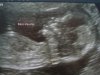

tu était a combien de mois pour la deuxieme éco?

on le voit très bien!!!